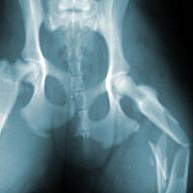

Artrose bij de kat komt vooral voor in gewrichten zoals de elleboog, schouder, heup, knie en wervels.

Artrose is een vorm van slijtage van gewrichten waardoor bewegingsproblemen en pijn kunnen ontstaan.